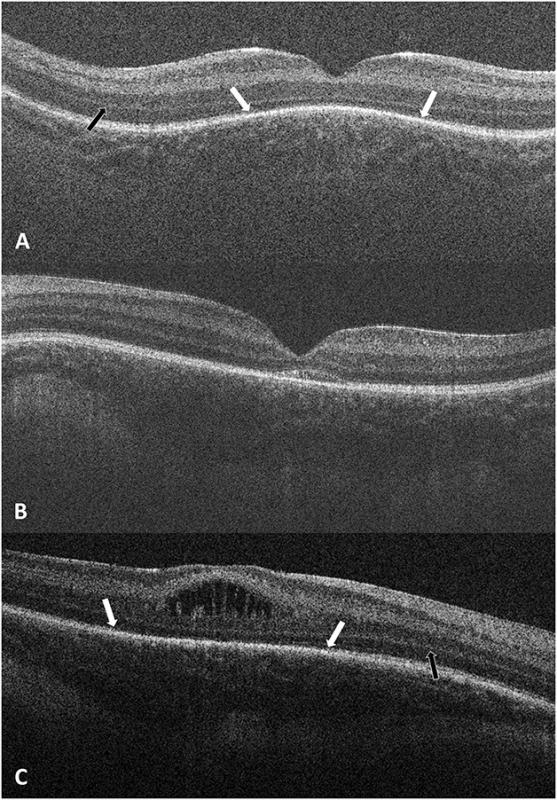

Medical Student Leads Study to Extend New Non-invasive Imaging Technology to Infants

Duke scientists found that a recently popularized non-invasive technology used to detect eye diseases in adults can also be used on infants.